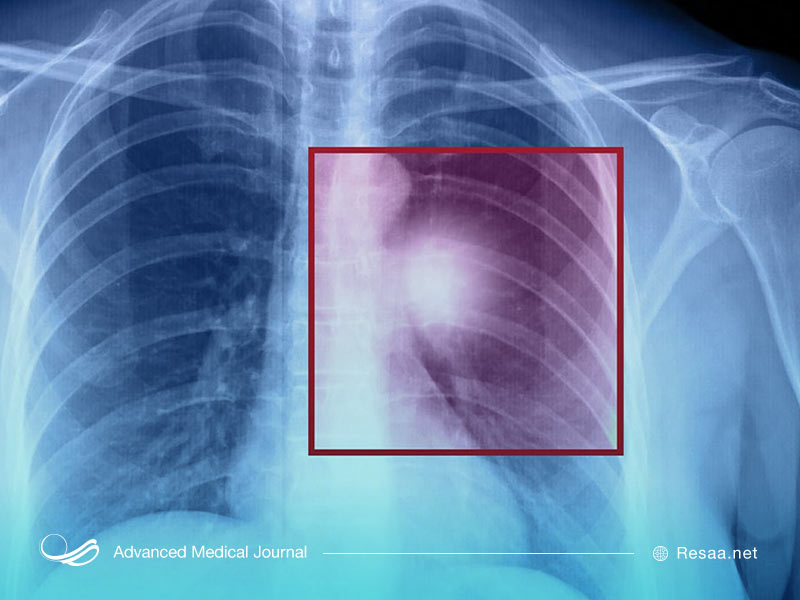

معمولاً، نگرانی از اینکه بیمار ممکن است به سرطان ریه مبتلا باشد، با یک مطالعه تصویربرداری شده از قفسه سینه از طریق اشعه ایکس یا سیتی اسکن تشخیص داده میشود. همچنین وقتی بیماری به اندازه کافی پیشرفت کند که باعث ایجاد علائمی مانند سرفه، تنگی نفس، درد قفسه سینه، خستگی و یا کاهش وزن شود نیز میتوان به بیماری را تشخیص داد.

تشخیص نیاز به بیوپسی یا خارج کردن سلولها یا بافتها از توده مشکوک دارد. بیوپسی را میتوان از طریق لولههای تنفسی به نام برونکوسکوپی یا از سوزنی که از طریق پوست وارد تومور ریه میشود، انجام داد. اگر این روشها موفقیتآمیز نباشند، ممکن است برای تشخیص به عمل جراحی نیاز باشد. در تعیین اینکه آیا سرطان وجود دارد یا خیر! و اصلاً چه نوعی است، انجام بیوپسی بسیار مهم میباشد.